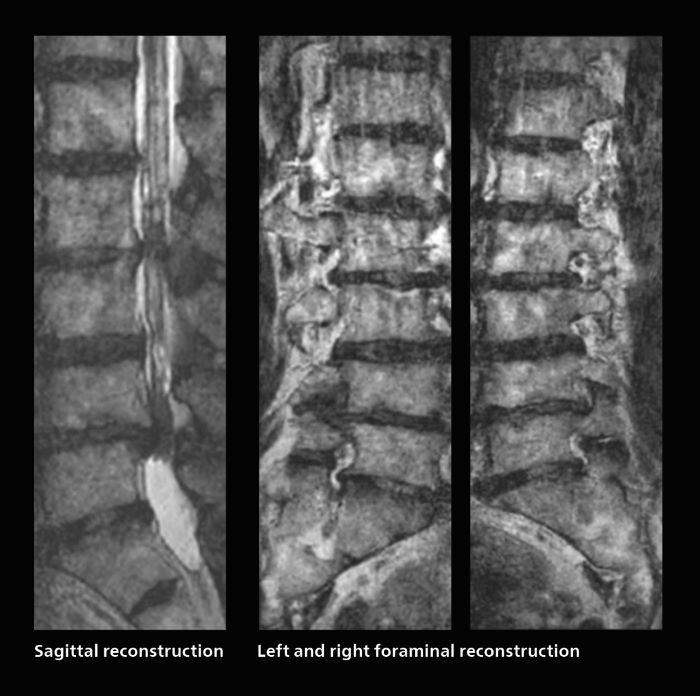

Many patients who must undergo a lumbar spine examination suffer from back pain. For these patients it is difficult to maintain the imaging position long enough to successfully complete the examination. “In such cases, using SmartSpeed allows us to perform volume imaging, so that we acquire only one high resolution 3D sequence in a short time and then reconstruct the other orientations from that,” Dr. Katahira says. “This is highly advantageous because the patient needs only endure a short exam time, whereas before it was necessary to acquire a larger number of sequences in total. We have seen that the shorter time has allowed us to scan patients who previously could not finish the exam. This is a great advantage.”

A patient arrived saying that undergoing MRI was not possible because of severe back pain and leg pain, was imaged with SmartSpeed in only 94 seconds. The scan was diagnostic and afterwards the patient confirmed that it only took a little while. Performed on Elition X.

The hospital’s fast lumbar spine ExamCard includes T2W SpineVIEW, 1:40 min, 1.0 mm isotropic, acceleration factor 12.